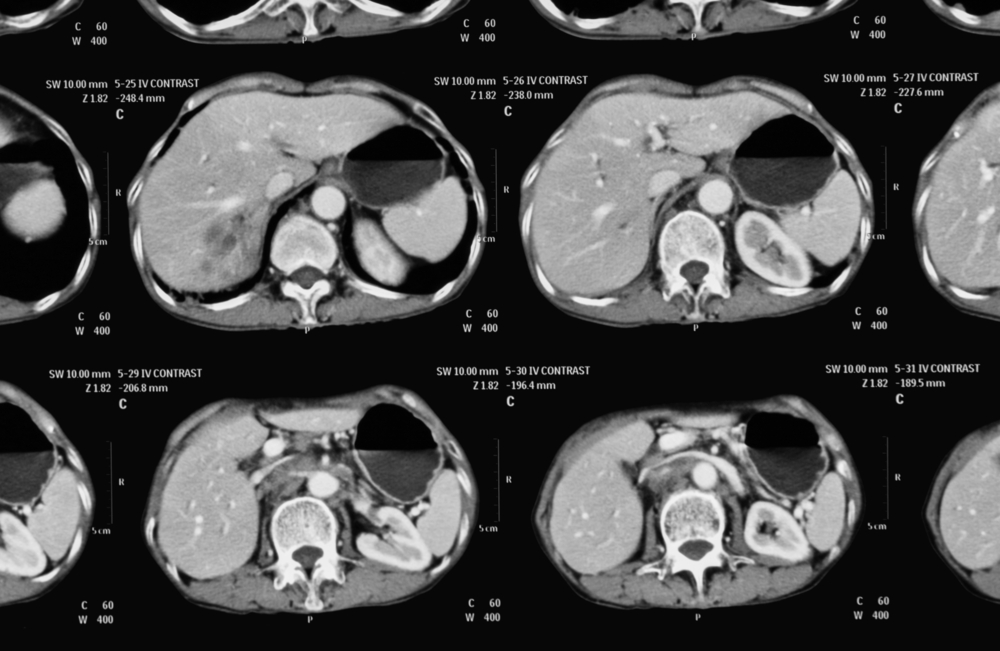

С целью подтверждения диагноза используются методы топической диагностики – компьютерная и магнитно-резонансная томография. Аппарат КТ выявляет новообразования надпочечников размерами более 10 мм, а МРТ обнаруживает опухоль даже менее 10 мм в диаметре.

УЗИ надпочечников малоинформативно, поскольку может обнаружить лишь крупную опухоль – размерами более, чем 2-3 см.

С целью топической диагностики, как и при других опухолях надпочечников, используют компьютерную или магнитно-резонансную томографию. При локализации феохромоцитомы вне надпочечников проводят сцинтиграфию (сканирование) с предварительным введением в организм вещества, накапливающегося в хромаффинной ткани, или ангиографическое исследование. УЗИ в данном случае малоинформативно.